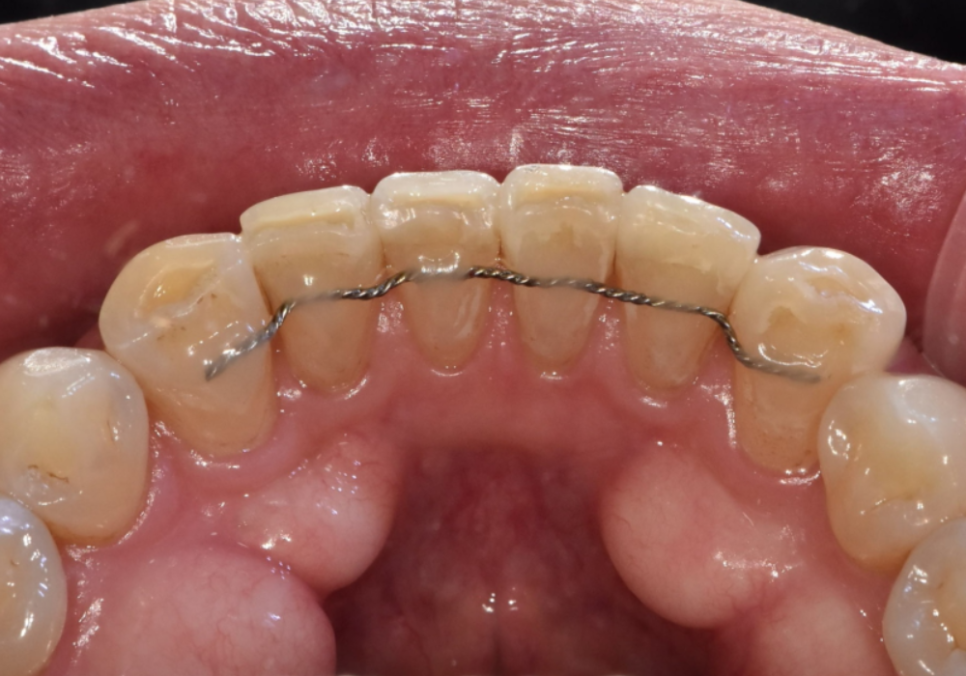

이때 꼭 잊지 말아야 할

아주 중요한 단계가 하나 더 있습니다.

바로 유지 장치입니다.

우리 치아는 원래 살던 자리로

돌아가려는 고집스러운 습성이 있습니다.

특히 교정 직후에는 치아 주변 조직들이

아직 완전히 자리를 잡지 않은 상태라,

관리를 소홀히 하면 공들여 만든

예쁜 배열이 다시 틀어질 수 있습니다.

250721

그래서 이번 환자분께도 앞니 안쪽에

아주 가느다란 철사를 붙여주는

'고정식 유지 장치'를 제작해 드렸습니다.

겉으로는 전혀 보이지 않고,

혀에 닿는 느낌도 금방 적응되기 때문에

일상생활이나 식사할 때

불편함 없이 치아 라인을 단단하게

지켜줄 수 있습니다.